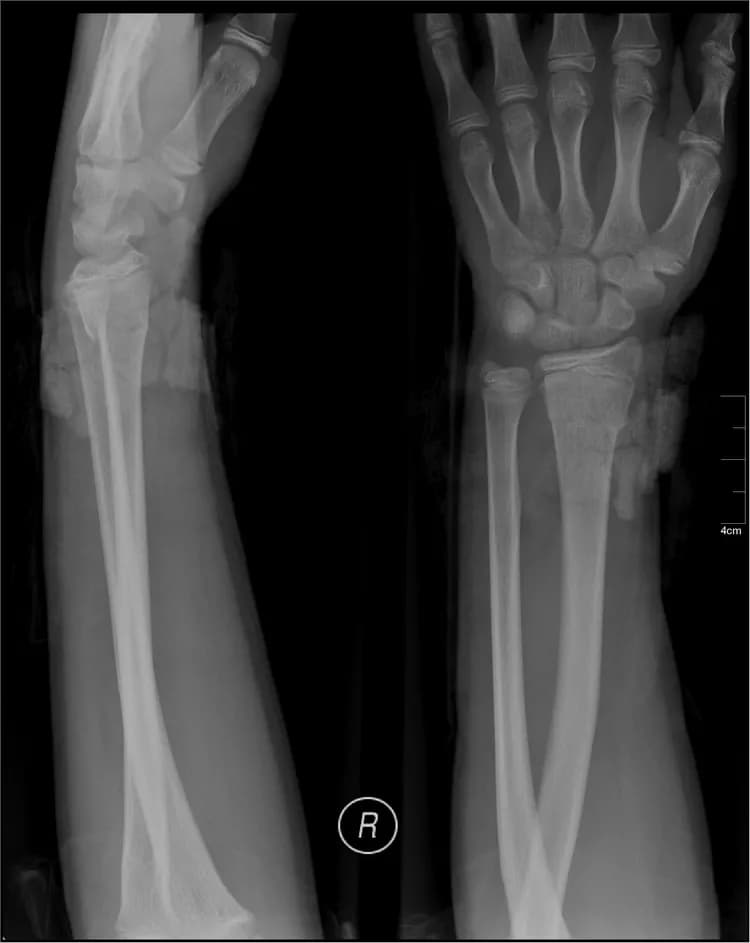

Test your knowledge on the medical condition Adult Forearm Fracture and learn more about its cause, symptoms, diagnosis, complications, treatment, prevention, and prognosis.